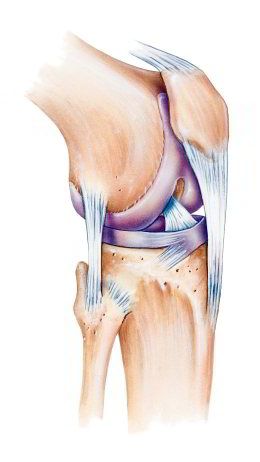

-- die Kniescheibe ist eine etwas dreieckige Scheibe mit Wölbung zum Schutz des Knies

-- die Kniescheibe wird von Sehnen oben und unten gehalten, oben am Oberschenkelmuskel angesetzt, unten am Schienbein angesetzt

-- dank der Kniescheibe und den Sehnen kann man das Bein in leichter Weise strecken

-- die Rückseite der Kniescheibe hat eine Knorpelschicht für das Gleiten beim Beugen und Strecken des Beines

-- im Alter bildet sich die Knorpelschicht zurück, so beginnt oft eine Kniearthrose

-- Schäden an der Kniescheibe können sein: Fehlbildung, Bruch, Entzündung [web01]

Schema Knie Querschnitt

Knie Schema mit dem Querschnitt [x1]

"Die Kniescheibe (Patella) ist ein flacher Knochen, der vor dem Kniegelenk liegt. Von vorne betrachtet hat die scheibenförmige Kniescheibe eine eher dreieckige Form mit einer leichten Wölbung nach vorn. Die Kniescheibe ist in die Sehne eingebunden, die am Oberschenkelmuskel ansetzt. Sie vergrößert damit die Hebelwirkung der Sehne und sorgt dafür, dass wir das Bein mit geringem Kraftaufwand des Oberschenkelmuskels strecken können. Außerdem schützt sie das Kniegelenk. Wenn wir das Knie strecken und wieder beugen, wandert die Kniescheibe mehrere Zentimeter über den Oberschenkelknochen. Deshalb ist die Rückseite der Kniescheibe mit einer dicken Knorpelschicht überzogen. Schäden an der Kniescheibe können sich aus Fehlbildungen ergeben, durch Bruch oder Entzündungen entstehen. Außerdem beginnt eine Kniearthrose häufig an der Kniescheibe." [web01]